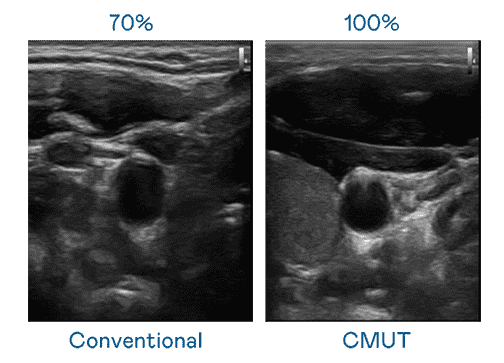

CMUT 技术是一种用电容式微机电元件来产生超音波讯号的技术。。。与传统 PZT 压电式技术相比,,,CMUT 频宽增加 30%,,,更宽频的超音波讯号让影像解析度大幅提升,,,是实现高影像品质医疗超音波扫描、、、、促进精准医疗发展的关键技术。。。。

大频宽带来超清晰影像

超音波影像的解析度高低,,,,首先取决于探头能发出的讯号频宽。。。YAXIN111 CMUT 可提供高清晰的超音波讯号,,,提供高频宽、、、高灵敏度、、影像纹理细节更高的超音波影像,,,,协助医护人员缩短影像判读时间及利用精准的医疗影像进行诊断。。。。